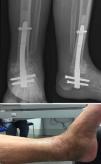

A los 2 meses del alta y de nuevo al comenzar carga parcial con ortesis, la paciente recae presentando úlcera medial y supuración activa por la misma, con imagen radiológica de rotura del espaciador (fig. 2). Ante esta nueva situación, se le plantea la amputación infrageniana reglada, pero la paciente y familiares la rechazan. Ante las distintas posibilidades, y con la intención de estabilizar el miembro y tratar la infección al mismo tiempo, se realiza mediante abordaje posterior transaquíleo de tobillo (por el mal estado de las partes blandas en cara anterior y lateral de tobillo), un nuevo desbridamiento, con acortamiento del miembro e implante de clavo retrógrado tibiotalocalcáneo modelo Expert-HAN® (DePuy-Synthes, España) cubierto de cemento con antibiótico (gentamicina+vancomicina+tobramicina, ver el apartado «Técnica quirúrgica») (fig. 3).

Técnica quirúrgicaPara determinar los antibióticos a utilizar, además de hacer una nueva toma de cultivos prequirúrgica, se deben revisar todos los cultivos positivos que ha presentado desde el inicio y emplear los antibióticos necesarios para cubrir todos los gérmenes aislados. En cuanto a las características de los antibióticos es fundamental que no sean termosensibles, y se prefiere presentaciones en polvo frente a líquido. La dosis adecuada de antibiótico global se recomienda entre 3,6 y 8g de antibiótico por cada 40g de polimetilmetacrilato, para tener propiedades terapéuticas y para no alterar las propiedades del cemento9,10. En este caso utilizamos 40g de polimetilmetacrilato Hi-Fatigue G Bone Cement (Zimmer®) que incluye 0,9g de sulfato de gentamicina (0,55g de gentamicina base), a la que añadimos 2,5g de vancomicina y 1,5g de tobramicina. Realizamos la preparación sobre el recipiente introduciendo en primer lugar el polvo del cemento, posteriormente el antibiótico en polvo y se mezcla, para después añadir el antibiótico en líquido y por último el líquido del cemento. Posteriormente se realiza el mezclado según técnica habitual pero se recomienda no usar vacío10. La mezcla se introduce en un tubo de silicona esterilizado (de 2mm de grosor superior al clavo a emplear) mediante la pistola de cemento, dejando salir el aire inicialmente por el extremo opuesto del tubo y al llegar el cemento a este se coloca un dedo para evitar su salida (fig. 3). Después se introduce el clavo (conectado a su guía de inserción) a través del tubo de silicona, asegurando que el clavo quede revestido uniformemente de cemento y que el extremo proximal de conexión del clavo quede libre de cemento, y se espera al fraguado. Con un bisturí se corta longitudinalmente la silicona obteniendo nuestro clavo cementado (fig. 3). Conectando la guía de los tornillos de bloqueo del clavo o a manos libres o con la ayuda de fluoroscopia, se perforan los orificios de bloqueo del clavo antes de ser implantado. Se implanta el clavo según técnica habitual, pero teniendo en cuenta que se trata de un clavo macizo sin posibilidad de aguja guía, y que el fresado debe ser para implantar un diámetro de 2mm más del diámetro del clavo sin cementar. En nuestro caso el clavo empleado fue un clavo con angulación en valgo fisiológico (Expert-HAN, Depuy-Synthes®) de 10mm de diámetro y 15cm de longitud, siendo la luz del tubo de silicona empleado de 12mm de diámetro. Por la forma del clavo de artrodesis de tobillo con mayor diámetro en la zona proximal (12,5mm) adaptamos la técnica de preparación realizando un corte en la zona de la silicona correspondiente para permitir mayor diámetro de recubrimiento eliminando el sobrante antes del fraguado.